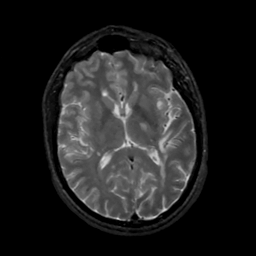

MR Study #5, March 10, 1991 -- Slice #28

[Home][Help][Clinical][Tour 1][Tour 2] Slice 28